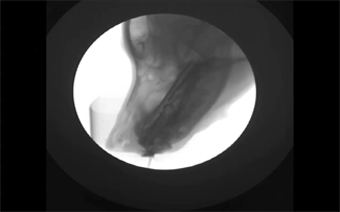

2. Con người trong một cuộc trò chuyện

Trung bình, mỗi người sử dụng 72 cơ để phát âm một từ. Quá trình phức tạp này được quét dưới một tia X. Bạn có thể đoán xem người đó đang nói gì không?